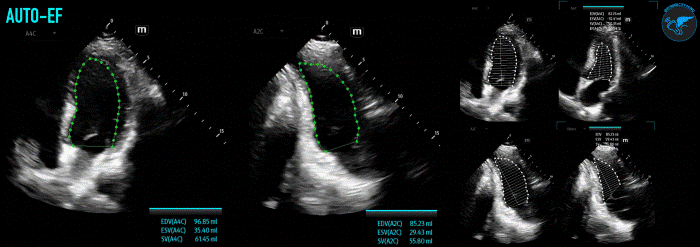

Simpson’s Biplane is the currently the most accurate echocardiographic measurement of LVEF, and is the American Society of Echocardiography recommended method/gold standard of measurement of LVEF by 2D echo.9 However, it should be mentioned that it is the most operator-dependent technique and can be potentially difficult and time-consuming when first learning. Accuracy of measurement is dependent on image quality and relies on adequate visualization of the endocardial border. One must also ensure to avoid foreshortening of the LV, as this will cause an underestimate of the LVEF. Biplane refers to the utilization of this method at two different planes, the A4C and apical 2 chamber (A2C) views. The measurement of LV volume at different angles takes more aspects of LV geometry into account helping minimize and improve overall accuracy.

To obtain this measurement, start in an A4C view. Focus and zoom in on the LV cavity to optimize visualization of the left ventricle. Freeze your image and find when the LV is at end-diastole (mitral valve closed, largest LV size). Starting at the medial mitral annulus, trace around the endocardial border (aka the blood-tissue interface) until you reach the lateral mitral annulus. Do not include the papillary muscles or trabeculations in your tracing. The contour of the tracing will be closed by a straight line between your starting and ending points at the mitral annulus. LV length is then measured from the middle point of the straight line across the mitral annulus to the most distal point of the LV apex. The ultrasound machine will then divide the LV cavity into multiple disks and calculate the end-diastolic volume (EDV). Next, freeze your image at end-systole (aortic valve close, smallest LV size) and repeat the previously mentioned steps to obtain the end-systolic volume (ESV). Using the EDV and ESV measurements, LVEF can then be calculated (LVEF,% = [(EDV-ESV)/EDV]×100). Finally, obtain an A2C view by rotating ~60° from the A4C view. Obtain the EDV and ESV at the A2C using the same steps as above (Figure 5).

Newer ultrasound machines may now also come with integrated auto-intelligence (AI) package functions that can assist in determining LVEF (Figure 6). Although these AI tools are enticing to use due to their ease of use and rapid results, it is important to first understand the basics on performance of these measurements to identify any inconsistencies or errors the machine may be making.

LVSF_Figure 6_AutoEF v1.gifFigure 6. Example of AutoEF Plus Smart Tool on Mindray TE X Ultrasound System.